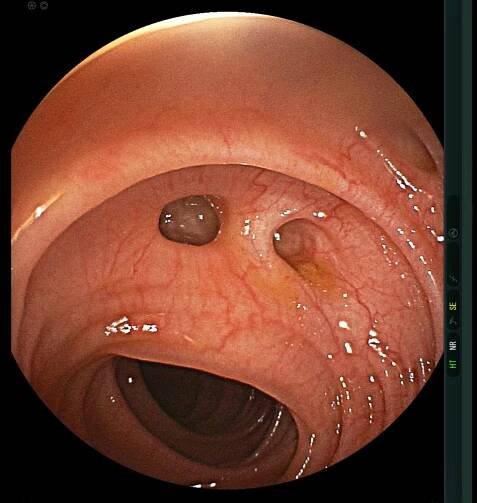

Segmental colitis associated with diverticulosis

Diverticulosis is the condition of having multiple pouches (diverticula) in the colon that are not inflamed. These are outpockets of the colonic mucosa and submucosa through weaknesses of muscle layers in the colon wall. [1 ] Diverticula do…